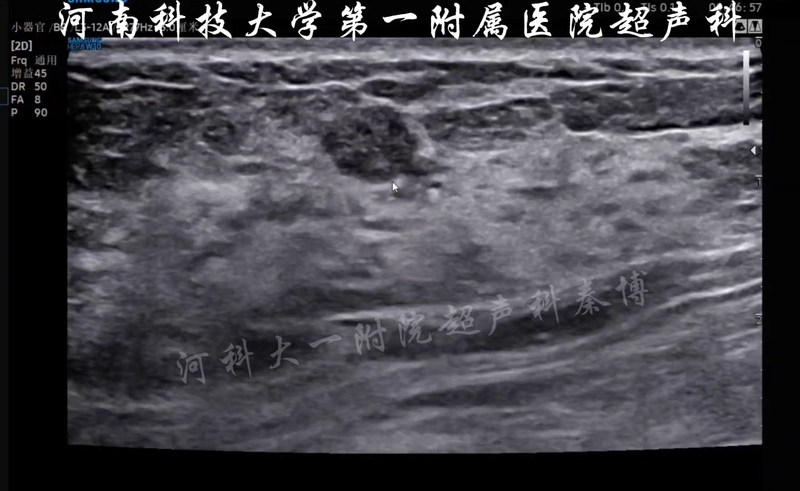

乳腺結(jié)節(jié)

秦博醫(yī)生的科普號2025年09月07日12